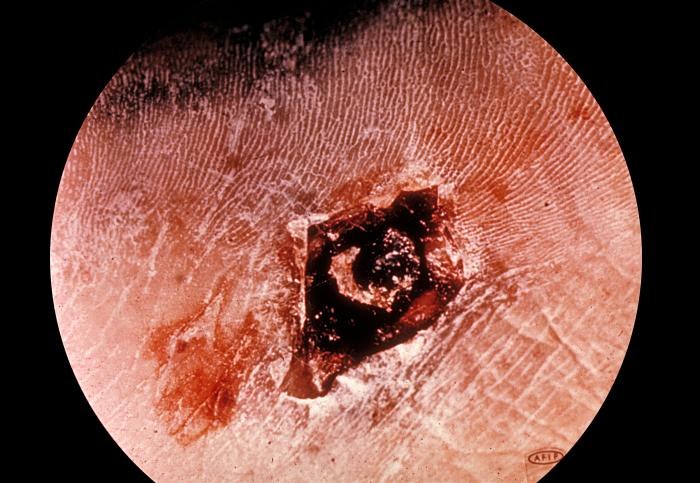

Diphtheria Photos

We have made these photos available for many vaccine-preventable diseases as an added resource. We list them separately from each disease’s main page. Learn more about diphtheria.